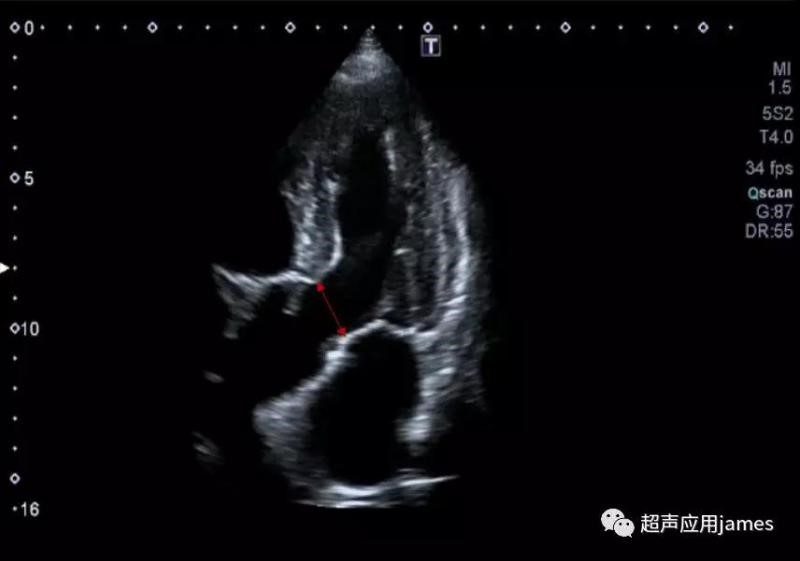

2.超声设备没有配置解剖M型功能,那么心尖上翘患者在左心室长轴切面还有另一种方法就是二维LV-Teich心功能测量方式:

3

采集步骤:获取最佳左室长轴的切面图像,然后冻结图像,启动双副图像,回放图像(左侧回放至舒张末期,右侧回放至收缩末期),打开心功能测量软件包,打开LV-Teich分别测量LVIDd和LVIDs就可得到EF、FS和SV等指标。此步骤的关键同时也是大家容易搞错的地方就是对于时相的选择,舒张末期和收缩末期一定都是二尖瓣和主动脉瓣同时关闭的时候,且保证两个图像在一个心动周期。